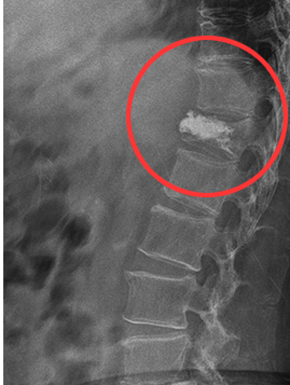

평상시 잘 사용하지 않던 몸을 사납게 사용하는 경우, 작은 바깥쪽 충격에도 뼈가 부러지는 등 골절을 겪기 쉬운 상태가 되요. 골절은 아무리 미세하고 약한 정도라도, 일상생활에 부담을 주고요.